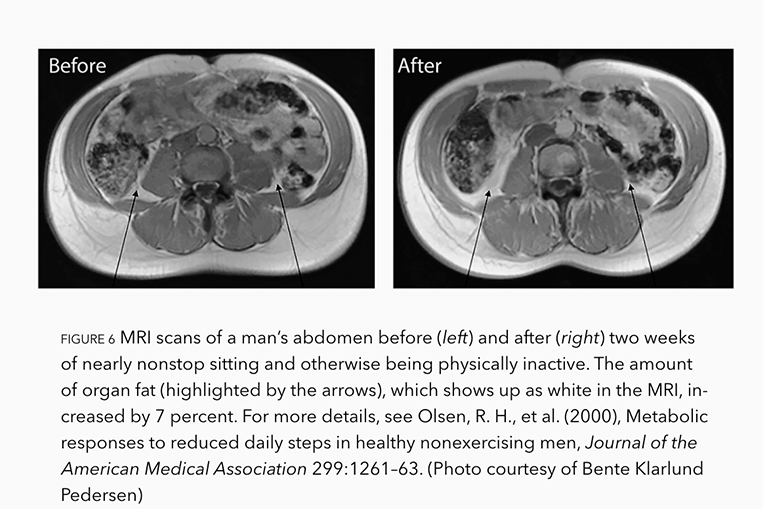

In one extraordinary experiment, Danish researchers paid a group of healthy young men to spend most of their day just sitting and restrict themselves to a maximum of 1500 steps a day for two whole weeks. Incredibly after just two weeks, they added an average of 7% more visceral fat to their organs, as indicated by the arrows in the Before and After photos.

And get this, as they gained this extra-dangerous organ fat, they also begin to exhibit the classic signs of inflammation, including insulin resistance.